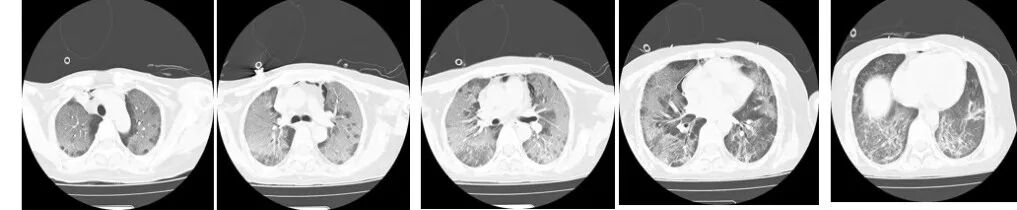

图1(2024年9月17日 D1)胸部CT示双肺弥漫性渗出性改变,伴磨玻璃影,实变影较少。